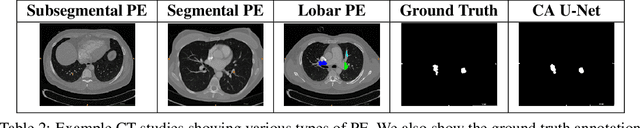

Abstract:Pulmonary Embolism (PE) is a life-threatening disorder associated with high mortality and morbidity. Prompt diagnosis and immediate initiation of therapeutic action is important. We explored a deep learning model to detect PE on volumetric contrast-enhanced chest CT scans using a 2-stage training strategy. First, a residual convolutional neural network (ResNet) was trained using annotated 2D images. In addition to the classification loss, an attention loss was added during training to help the network focus attention on PE. Next, a recurrent network was used to scan sequentially through the features provided by the pre-trained ResNet to detect PE. This combination allows the network to be trained using both a limited and sparse set of pixel-level annotated images and a large number of easily obtainable patient-level image-label pairs. We used 1,670 sparsely annotated studies and more than 10,000 labeled studies in our training. On a test set with 2,160 patient studies, the proposed method achieved an area under the ROC curve (AUC) of 0.812. The proposed framework is also able to provide localized attention maps that indicate possible PE lesions, which could potentially help radiologists accelerate the diagnostic process.

Abstract:Pulmonary embolisms (PE) are known to be one of the leading causes for cardiac-related mortality. Due to inherent variabilities in how PE manifests and the cumbersome nature of manual diagnosis, there is growing interest in leveraging AI tools for detecting PE. In this paper, we build a two-stage detection pipeline that is accurate, computationally efficient, robust to variations in PE types and kernels used for CT reconstruction, and most importantly, does not require dense annotations. Given the challenges in acquiring expert annotations in large-scale datasets, our approach produces state-of-the-art results with very sparse emboli contours (at 10mm slice spacing), while using models with significantly lower number of parameters. We achieve AUC scores of 0.94 on the validation set and 0.85 on the test set of highly severe PEs. Using a large, real-world dataset characterized by complex PE types and patients from multiple hospitals, we present an elaborate empirical study and provide guidelines for designing highly generalizable pipelines.